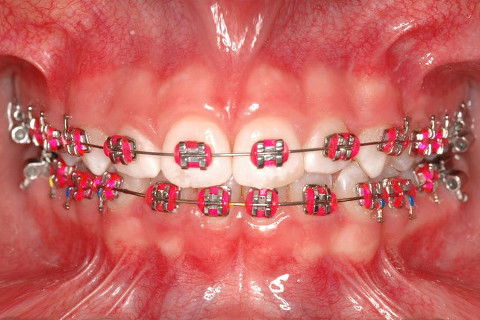

FINALIZAÇÃO; ELÁSTICO DE CLASSE II DUPLO.

FINALIZAÇÃO; ELÁSTICO DE CLASSE II SIMPLES.